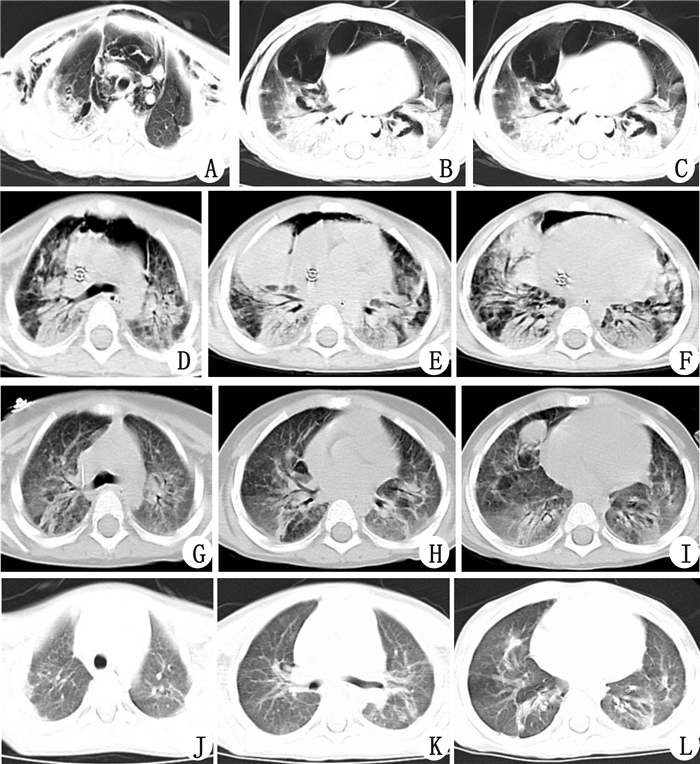

2.2 并发症及预后3例有置管处出血,其中1例ECMO第10天因DIC、失血性休克死亡;1例患儿反复溶血伴肾功能损害在ECMO同时行持续肾脏替代治疗(CRRT),后继发血培养阳性的严重脓毒症,虽经血液灌流等积极治疗,于ECMO第24天因多脏器功能衰竭死亡;1例患儿ECMO上机后抽搐2次,临床考虑缺氧缺血性脑损伤可能,予德巴金治疗后未再抽搐,该患儿成功脱离ECMO后12 d因继发呼吸机相关性肺炎,再次出现难治性低氧血症死亡。2例存活患儿除高血压外无严重并发症,经药物降压后血压维持正常,出院随访至今(9~13个月),活动耐量及肺功能基本正常,头颅MRI、MRA及脑电图无明显异常。5例患儿并发症及预后见表 1,第5例患儿治疗前后的胸部CT变化见图 1。

| A~C:入院第3天胸部CT提示双肺弥漫性密度增高影,皮下及纵隔积气;D~F:入院第19天,ECMO第10天胸部CT提示双肺广泛斑片影,右肺中叶见致密片状影,纵隔积气;G~I:入院第74天,ECMO撤机后46 d胸部CT提示双肺斑片影较前减少,双肺纹理增多模糊;J~L:出院第92天,胸部CT提示肺炎恢复期,轻度肺纤维化 图 1 例5患儿ECMO前后胸部CT变化 |